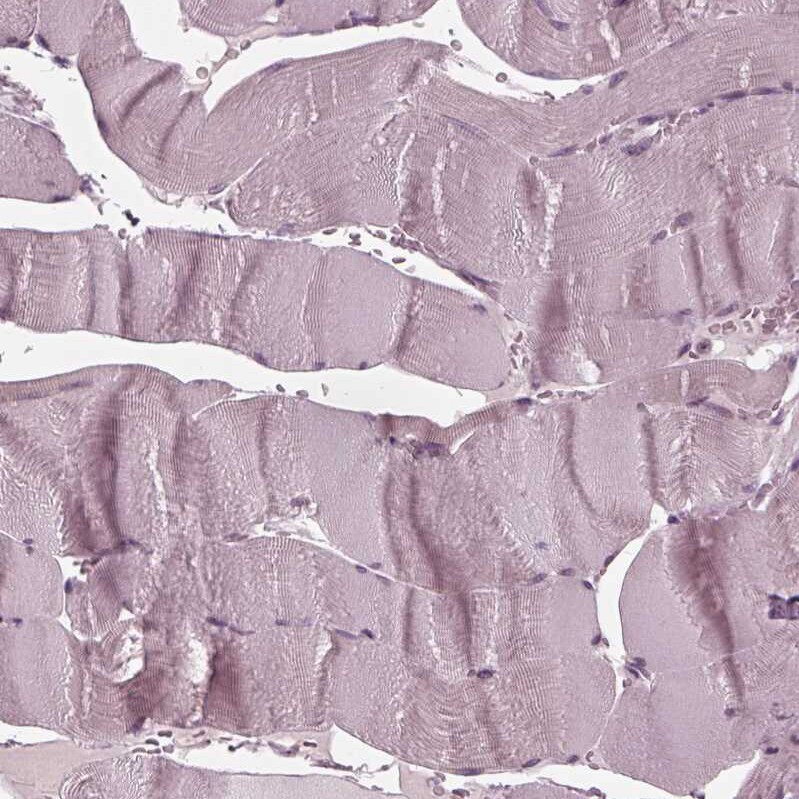

- Submitted by

- Invitrogen Antibodies (provider)

- Main image

- Experimental details

- Immunohistochemical analysis of FAM154A in human skeletal muscle using FAM154A Polyclonal Antibody (Product # PA5-54919) shows no positivity in myocytes as expected.